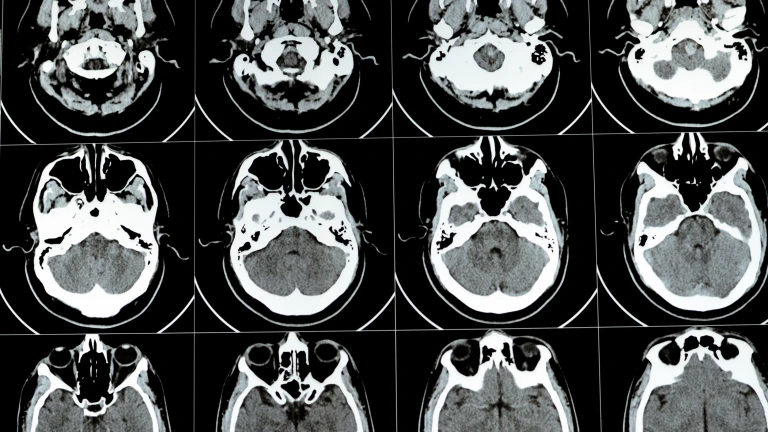

Imagen de recurso